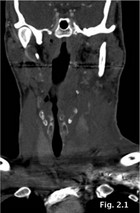

A contrast-enhanced CT-scan of the head and neck was performed. This showed complete laceration of the left lobe of the thyroid gland, which was transected into an upper and a lower portion. No contrast extravasation - a sign of active bleeding - was present at this time. The left superior thyroid artery was not injured and perfusion of the upper fragment of the left split thyroid gland was intact.

The situation was similar in the lower fragment, which was fed by the inferior thyroid artery (Fig. 2).The larynx and trachea did not show any abnormalities.